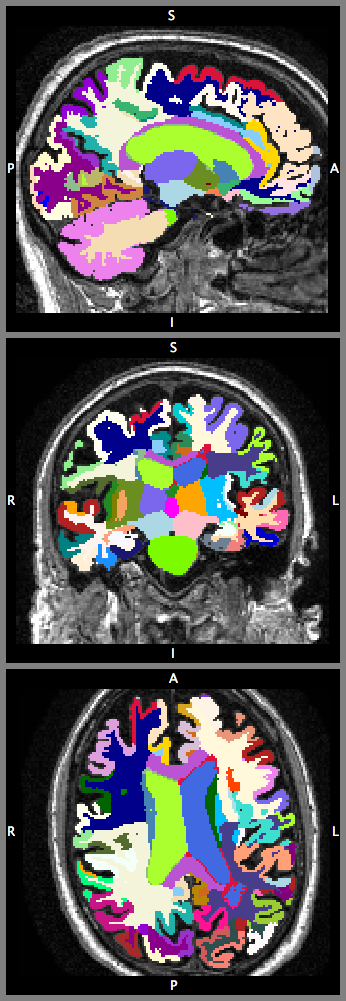

To demonstrate the feasibility of learning complex 3D image representations from large-scale data, the proposed network is learning a highly granular segmentation of T1-weighted MR images of healthy controls from the ADNI dataset. The average number of voxels of each volume is about . The average voxel size is approximately . All volumes are bias-corrected and reoriented to a standard Right-Anterior-Superior orientation. The bronze standard parcellation of brain structures and non-brain outer tissues are obtained using the GIF framework [1]. Fig. 5(left) shows the label distribution of the dataset. We randomly choose 443, 50, and 50 volumes for training, test, and validation respectively.

In this section, we compare the proposed high-resolution compact network architecture (illustrated in Fig. 3; denoted as HC-default) with three variants: (1) the HC-default configuration without the residual connections, trained with cross-entropy loss function (NoRes-entropy); (2) the HC-default configuration without residual connections, trained with Dice loss function (NoRes-dice); and (3) the HC-default configuration trained with an additional dropout layer, and makes predictions with a majority voting of Monte Carlo samples (HC-dropout). For the dropout variant, our dropout layer employed before the last convolutional layer consists of kernels.

We use the mean Dice Coefficient Similarity (DCS) as the performance measure. Table LABEL:overall_cmp and Fig. 5(right) compare the performance on the test set. In terms of our network variants, the results show that the use of Dice loss function largely improves the segmentation performance. This suggests that the Dice loss function can handle the severely unbalanced segmentation problem well. The results also suggest that introducing the residual connections improved the segmentation performance measured in mean DCS. This indicates that the residual connections are important elements of the proposed network. By adopting the dropout method, the DCS can be further improved by 2% in DCS.